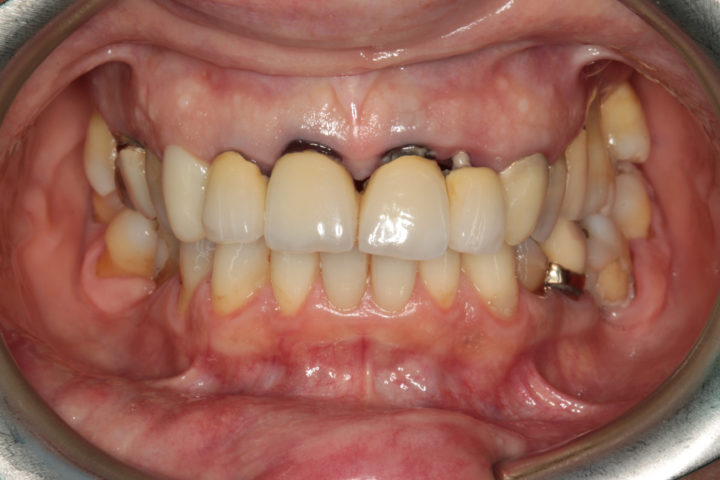

Riabilitazione di un vecchio ponte

Rimozione del ponte esistente con monconi cariati, esecuzione di estrazioni dentarie mirate, rigenerazione ossea guidata, e completamento del trattamento con un ponte in ceramica supportato da impianti in titanio.